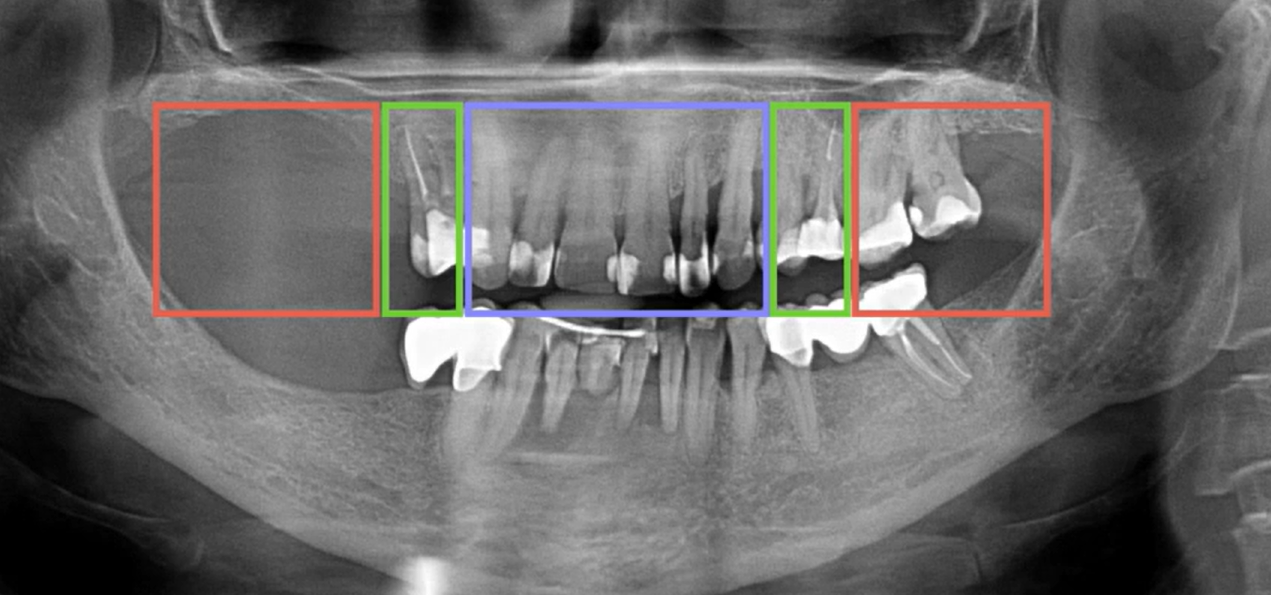

Let’s return to the photo from the previous part.

initial orthopantomogram of the patient. Full-arch prosthetics with support on implants is planned. YouTube/ Dr. Sergey Rozhnov /sergiodontolog

Here you can see the height of the teeth and the changes in the bone tissue that will need to be addressed. Of course, in most cases, the original occlusion should be maintained and the bite should not be “played with.” In this clinical case, the alveolar process will need to be leveled and some bone will need to be trimmed in the incisor area. Therefore, it’s easy to assume that the height of the prosthetic structure with abutments will be quite large.